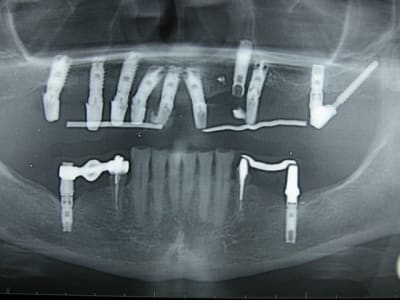

dans le style exotique..certes pas de MCI mais pas mal quand même.... adressé par un ami un peu dépassé par le cas qui se présentait... le travail était bien entendu la prothèse définitive... et de l'amalgame réunit les deux implants extrêmes...